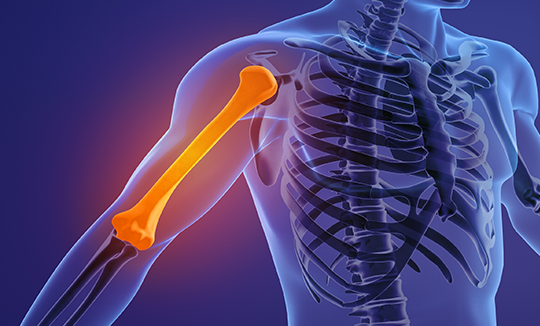

어깨골절은 상완골, 쇄골, 견갑골 등 어깨관절을 구성하는

뼈가 부러지는 것을 말합니다.

상완골 골절

상완골 골절은 어깨에서 팔꿈치까지 이르는 긴 팔뼈인 상완골이 부러진 상태입니다.

골절의 발생 위치에 따라 크게 세 가지로 분류됩니다.

• 1

근위부 골절 :

상완골을 1/3으로 나누었을 때 어깨 쪽에 가까운 부분의 골절

• 2

간부 골절 :

상완골을 1/3으로 나누었을 때 중간 부분 골절

• 3

원위부 골절 :

상완골을 1/3으로 나누었을 때 팔꿈치 쪽에 가까운 부분의 골절